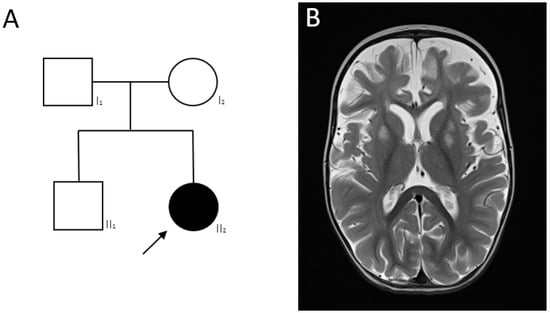

2.4. Clinical Cases